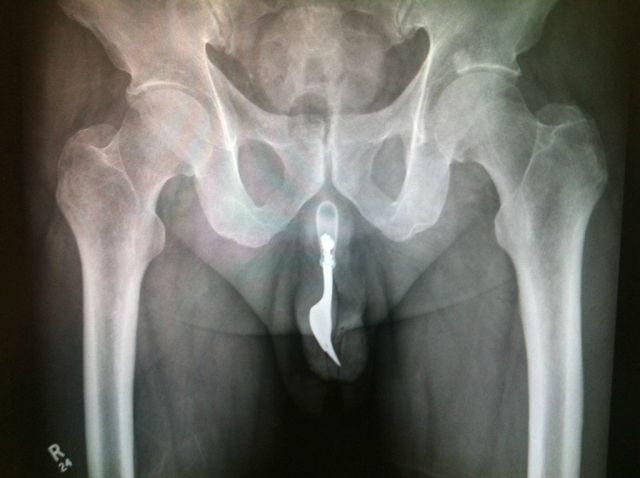

A fork. In the penis.